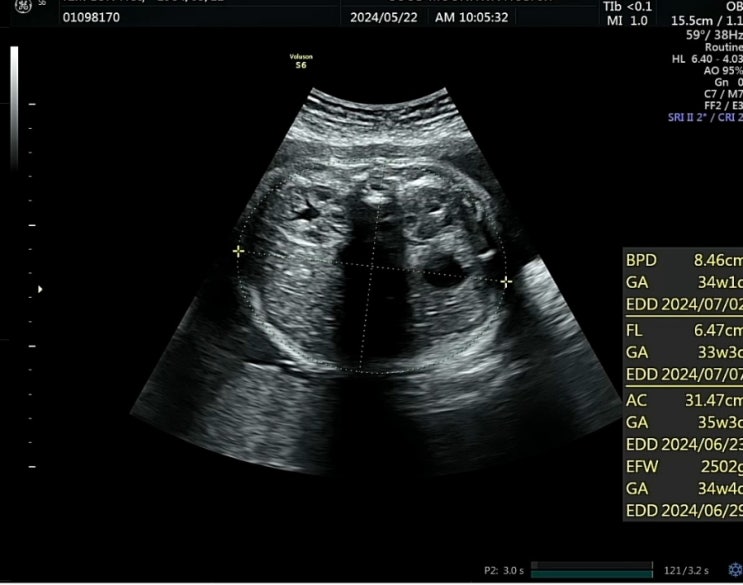

막달검사 완료 35주6일

태동 검사와 초음파를 보고 왔는데요. 일단 저번에 검사한 막달검사는 다 이상이 없다고 하시더라고요. ^^ ...